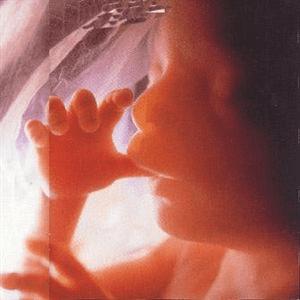

此时胎儿已长到四个半月,他移动手臂,把手指放在唇边,这可以促进它对吮吸的反映。

小小生命